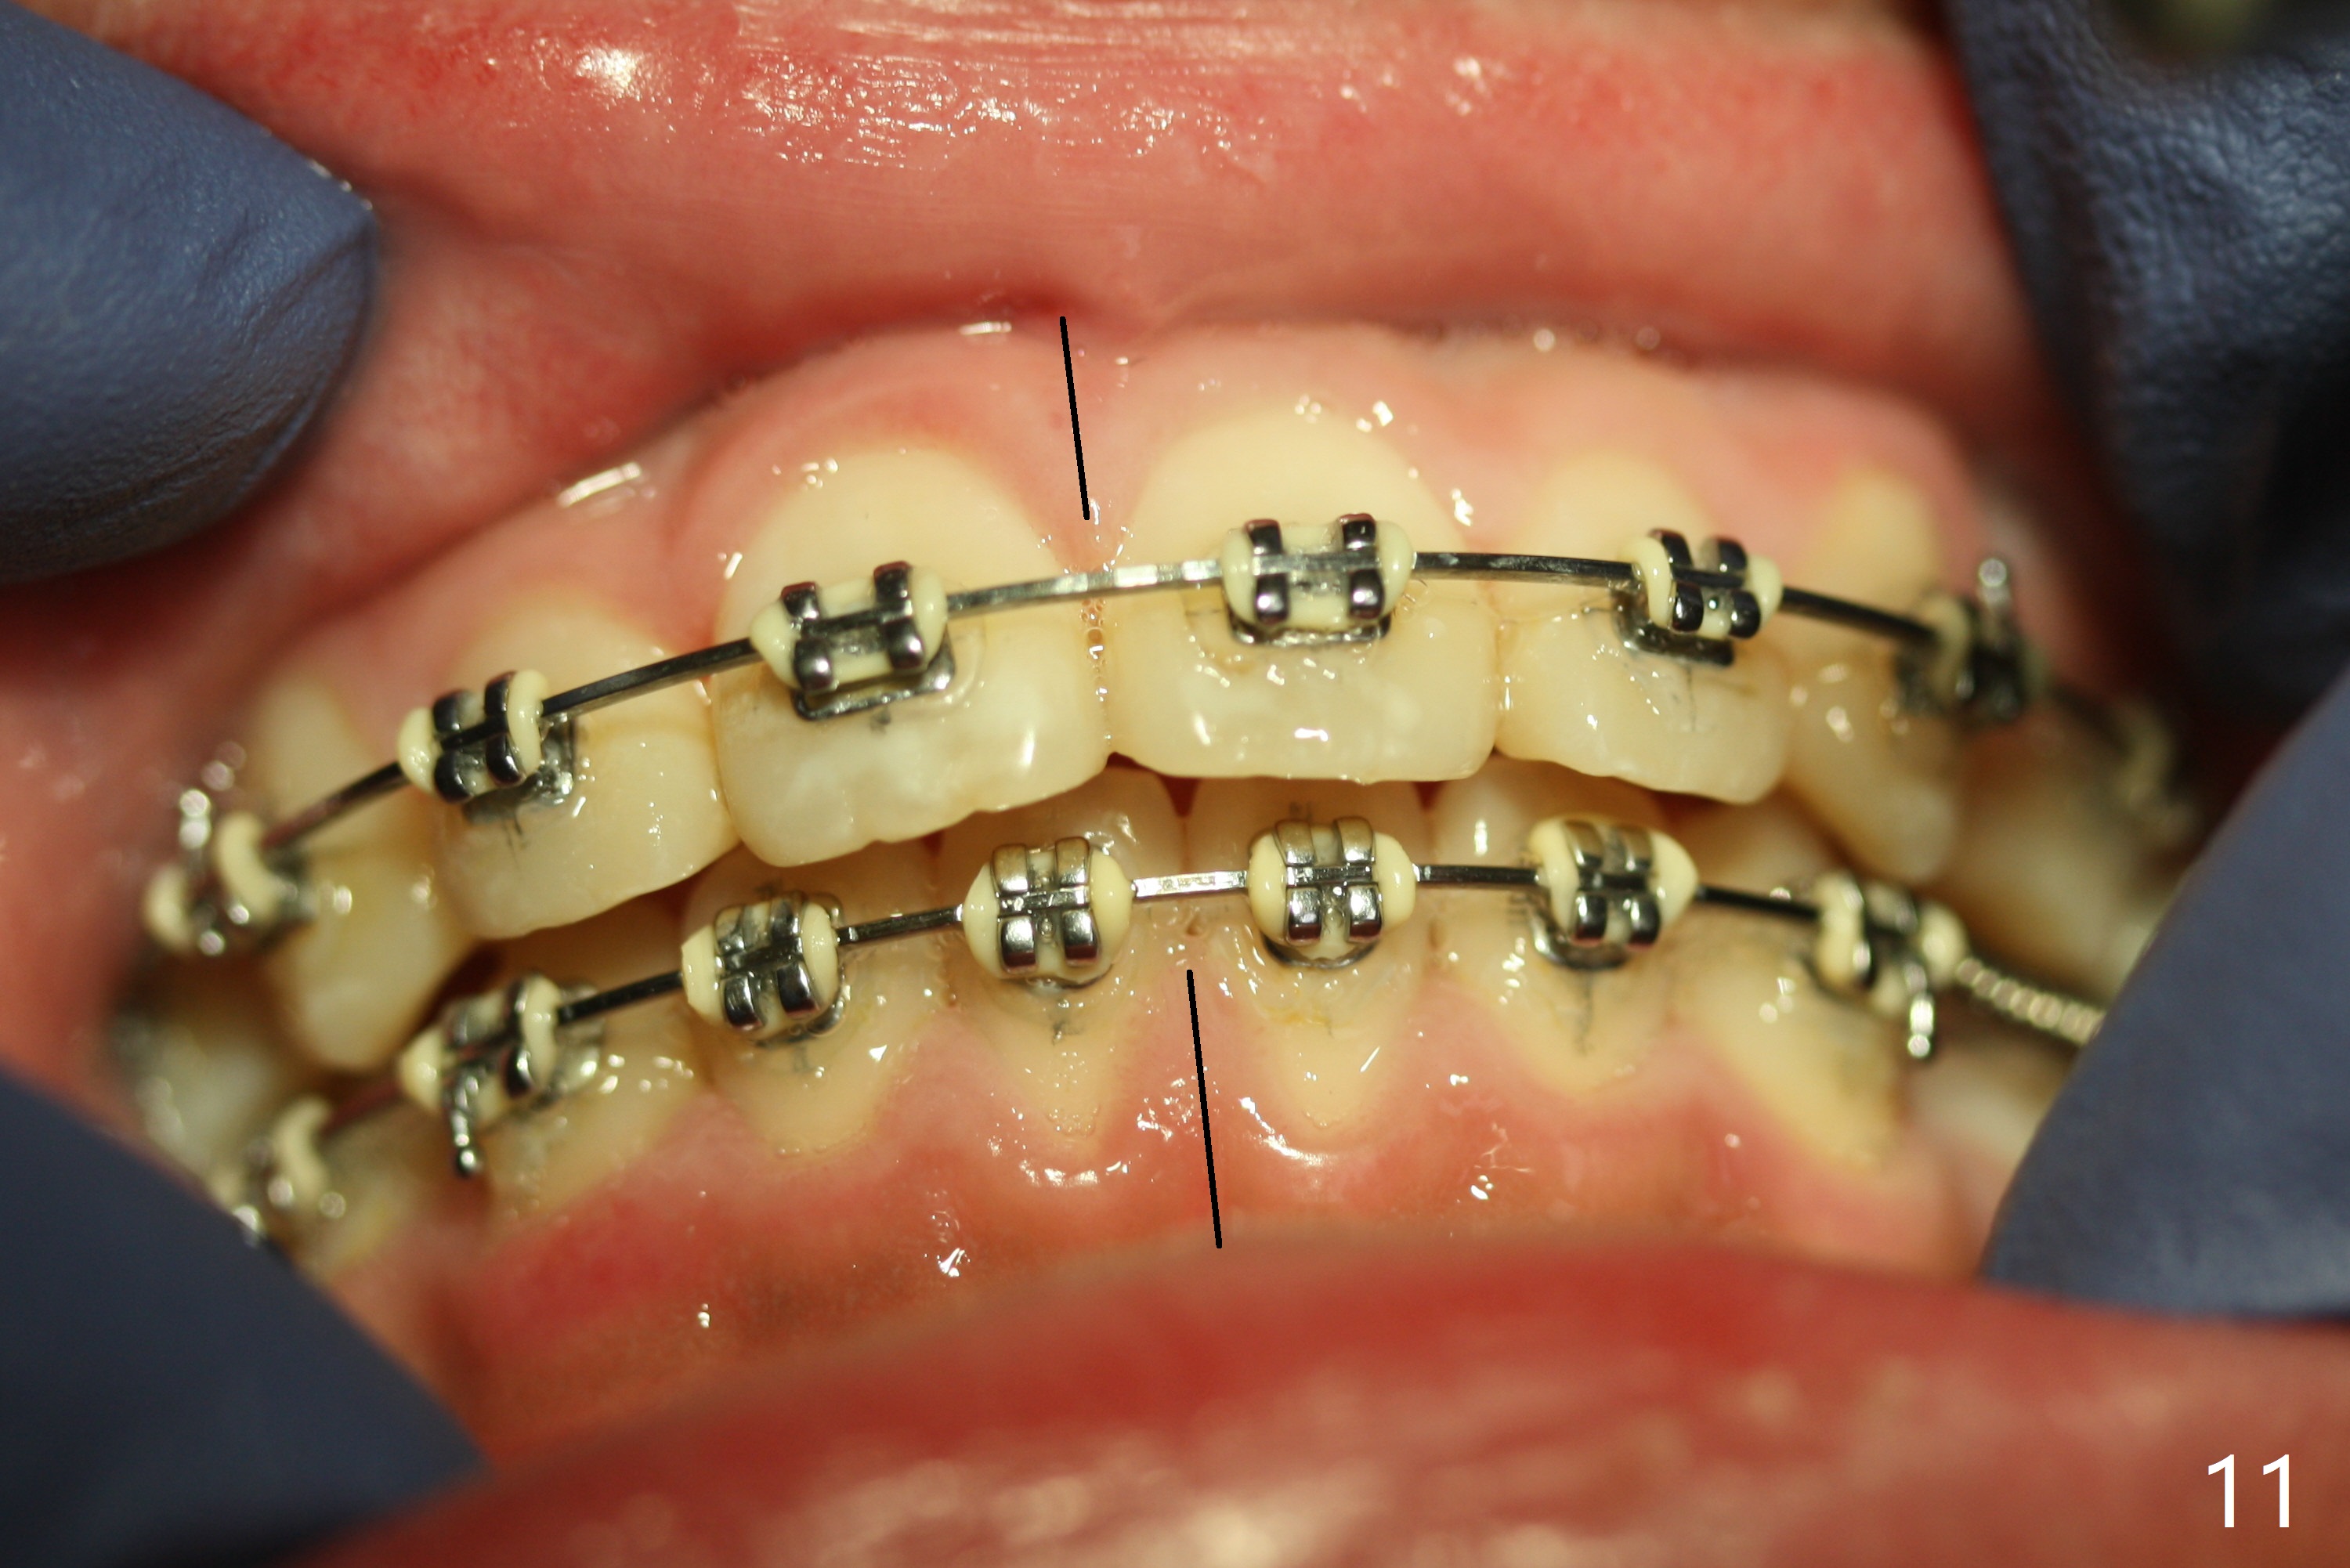

Eight months post banding, the interdigitation on the right side seems to be within normal limit (Fig.10), while the lower dental midline appears to be deviated to the left (Fig.11) with anterior overjet (Fig.12). The left canines remain Class II; open coil spring is placed between LL3-6 with intention to reduce anterior overjet and correct the lower midline deviation (Fig.13). Four weeks later, LL3 does not seem to be mesialized. It appears that the long open coil spring between LL3-6 is not effective. A molar band is added to LL E (Fig. 14,15). When a molar band is placed in LL7, an upper niti wire will be placed in the lower arch to expand the arch. When arch wire turns into thicker one, place open coil spring between LL3 and E.